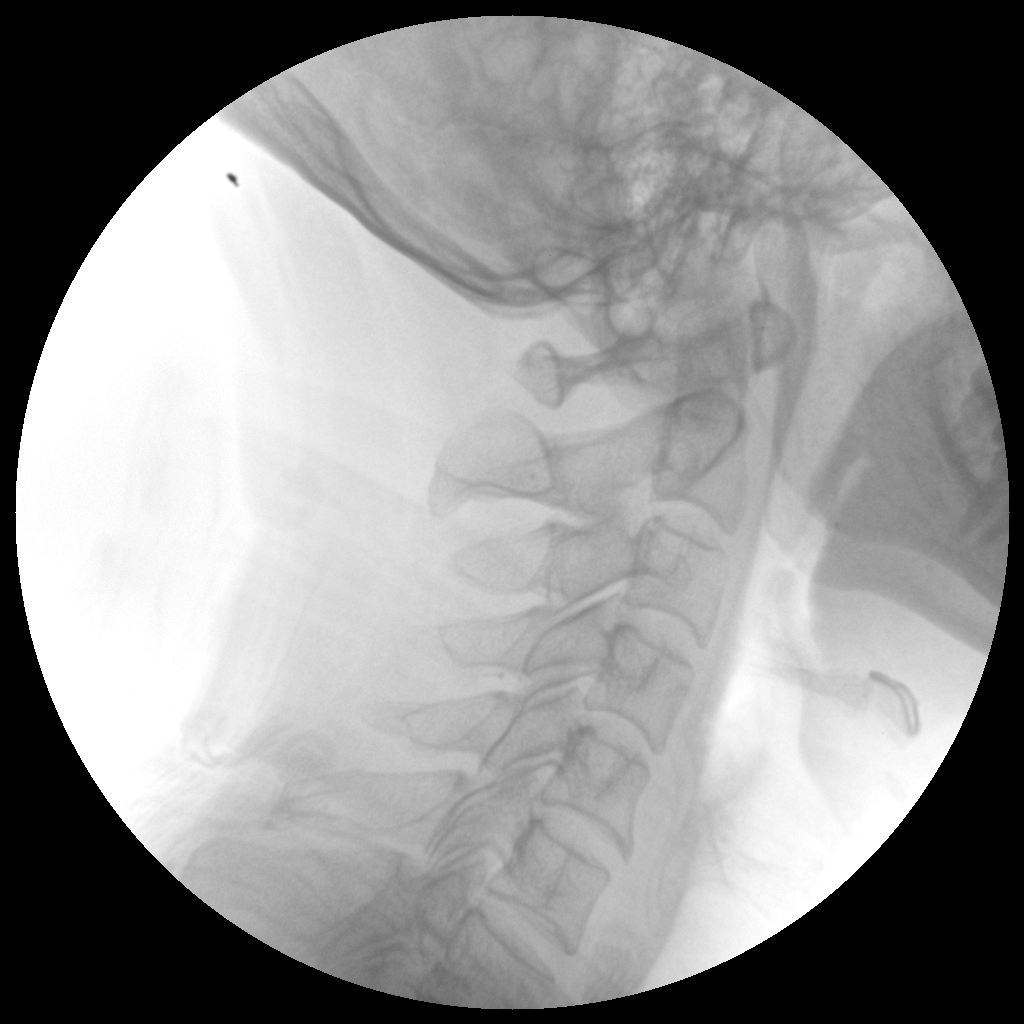

●全數(shù)字化百萬(wàn)像素影像系統(tǒng),圖像清晰

●靈活的C臂機(jī)架設(shè)計(jì),滿足臨床大范圍運(yùn)動(dòng)